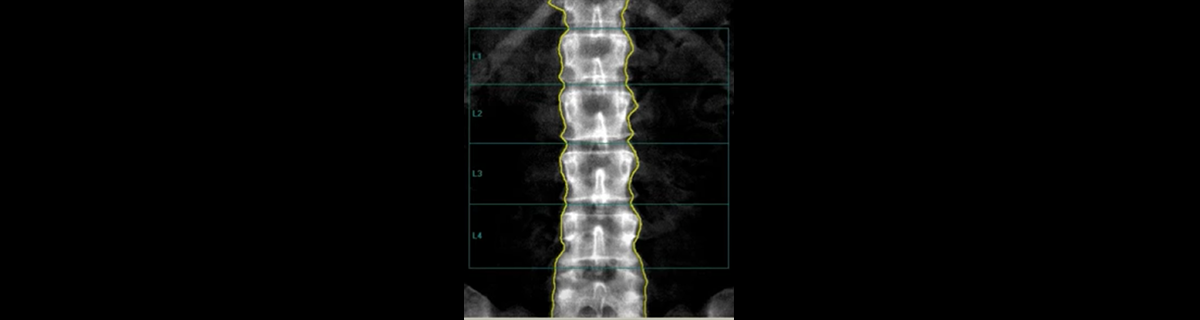

Dual energy X-ray absorptiometry (DXA) scans are routinely used to measure patients bone density levels and screen for osteoporosis, but clinicians need more information to make an accurate assessment of their level of fracture risk and whether to recommend treatment for their patients. The introduction of Trabecular Bone Score (TBS) to estimate patients’ bone texture, which in combination with bone density, provides important additive information to help clinicians predict fracture risk.

An FDA cleared software with TBS functionality, TBS uses DXA scans to estimate bone texture and assess bone micro architecture, providing additive information to bone mineral density (BMD). TBS is a separate risk factor from bone density that measures bone quality and research suggests that it adds to DXA in predicting patients whose bones are at risk of fracture due to diseases or medications they are taking. According to Professor Hans, two patients can have the same bone density T-score, but different bone structure and therefore different fracture risk.